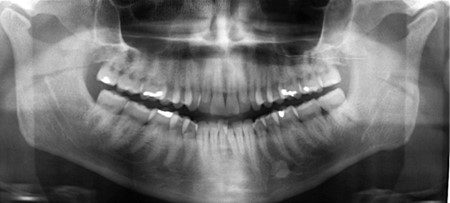

Trước khi tập trung vào bất kỳ phân tích đo lường nào, cần phải sàng lọc kỹ từng phim X-quang để phát hiện các dấu hiệu bệnh lý. Nhiều hình ảnh bệnh lý thường không được phát hiện bởi bác sĩ lâm sàng, do sự chú ý thường tập trung vào phân tích chỉnh nha hơn là các cấu trúc giải phẫu. Người ta phát hiện có đến 6% bệnh nhân chỉnh nha có những bất thường hoặc tổn thương bệnh lý nào đó trên phim X-quang chẩn đoán chỉnh nha (hình 1-44).

Hình 1-44. Hình dạng lồi cầu trên phim toàn cảnh gợi ý các thay đổi do thoái hóa khớp (thoái hóa khớp thái dương hàm – osteoarthritis). Cũng lưu ý có một cấu trúc cản quang giữa chóp răng của hai răng cối nhỏ hàm dưới bên trái – tương ứng với tình trạng xơ cứng vô căn (idiopathic osteosclerosis).